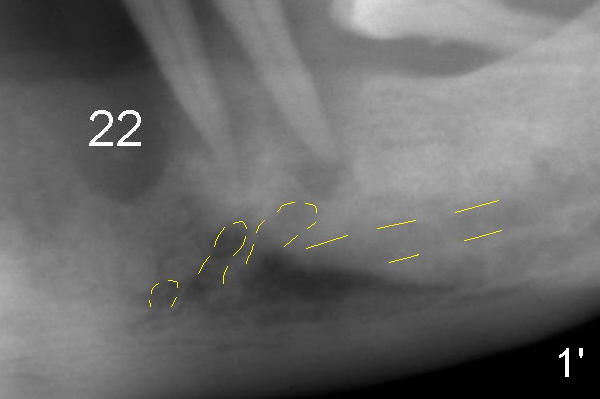

Fig.1: There appears to be triple mental nerve loops below the lower left canine and premolars. Return to